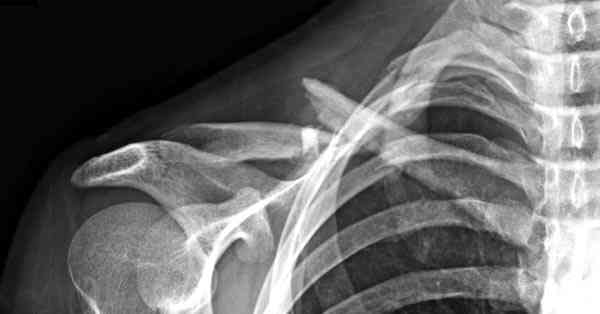

iГГШ> выполнения новокаиновой блокады дежурной бригадой выполнена закрытая

ГГШ> репозиция, наложены кольца Дельбе. Результаты репозиции показаны на

Судя по проекциям ключицы, очевидно разобщение фрагментов, чаще всего сопровождающееся интерпозицией платизмой. для 15 летнего пациента, категории физически активных пациентов выбрал бы оперативный метод( интрамедуллярно

винтом с частичной резьбой).

Для выбора метода лечения перелома ключицы при первичном обращении рутинно необходимо выполнение Рг графии в двух проекциях. принимать решение о

тактике лечения перелома, руководствуясь только одной передне-задней проекцией ошибочно( почему-то в отношении ключицы подобная недооценка

перелома наиболее часто встречается).